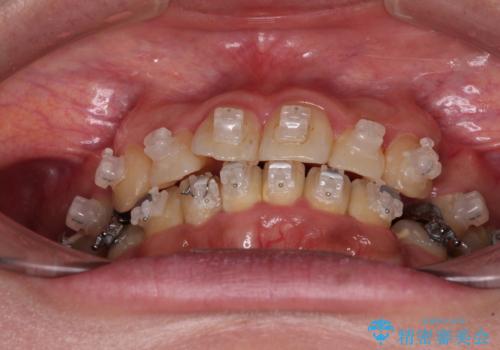

- 海外で抜歯矯正を開始し、治療途中で帰国したため、転院先を探しているとのことで来院された患者様です。

ワイヤーは抜けてしまい、後戻りが始まっている状態でしたが、既存の装置を継続利用して受け入れてくれる医院が見つからないとのことでした。

当院では、張り替える必要のある部位は張り替えることで継続することとし、抜歯スペースを閉じていくように治療を行うこととしました。